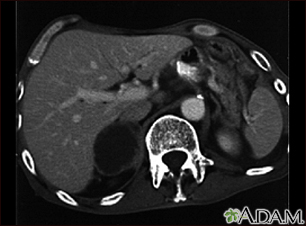

Adrenal metastases - CT scan